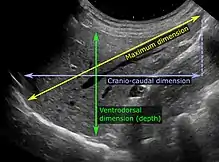

On abdominal ultrasonography, the liver can be measured by the maximum dimension on a sagittal plane view through the midclavicular line, which is normally up to 18 cm in adults.[2] It is also possible to measure the cranio-caudal dimension, which is normally up to 15 cm in adults.[2] This can be measured together with the ventro-dorsal dimension (or depth), which is normally up to 13 cm.[2] Also, the caudate lobe is enlarged in many diseases. In the axial plane, the caudate lobe should normally have a cross-section of less than 0.55 of the rest of the liver.[2]

Other ultrasound studies have suggested hepatomegaly as being defined as a longitudinal axis > 15.5 cm at the hepatic midline, or > 16.0 cm at the midclavicular line.[17][18]